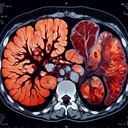

МРТ печінки

МРТ печінки — це неінвазивний діагностичний метод, що використовує магнітні поля та радіохвилі для отримання детальних зображень печінки і прилеглих структур. Ця процедура допомагає виявити аномалії, такі як пухлини, жирову інфільтрацію, фіброз чи інші ураження. Переваги МРТ печінки: - Висока роздільна здатність зображень...